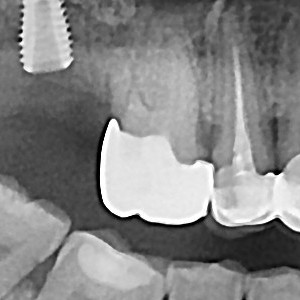

충치치료&신경치료 하루에 끝나는 신경치료

ab84f1a97a55df0651436bf31adcdd0f_1767396700_1056.jpg